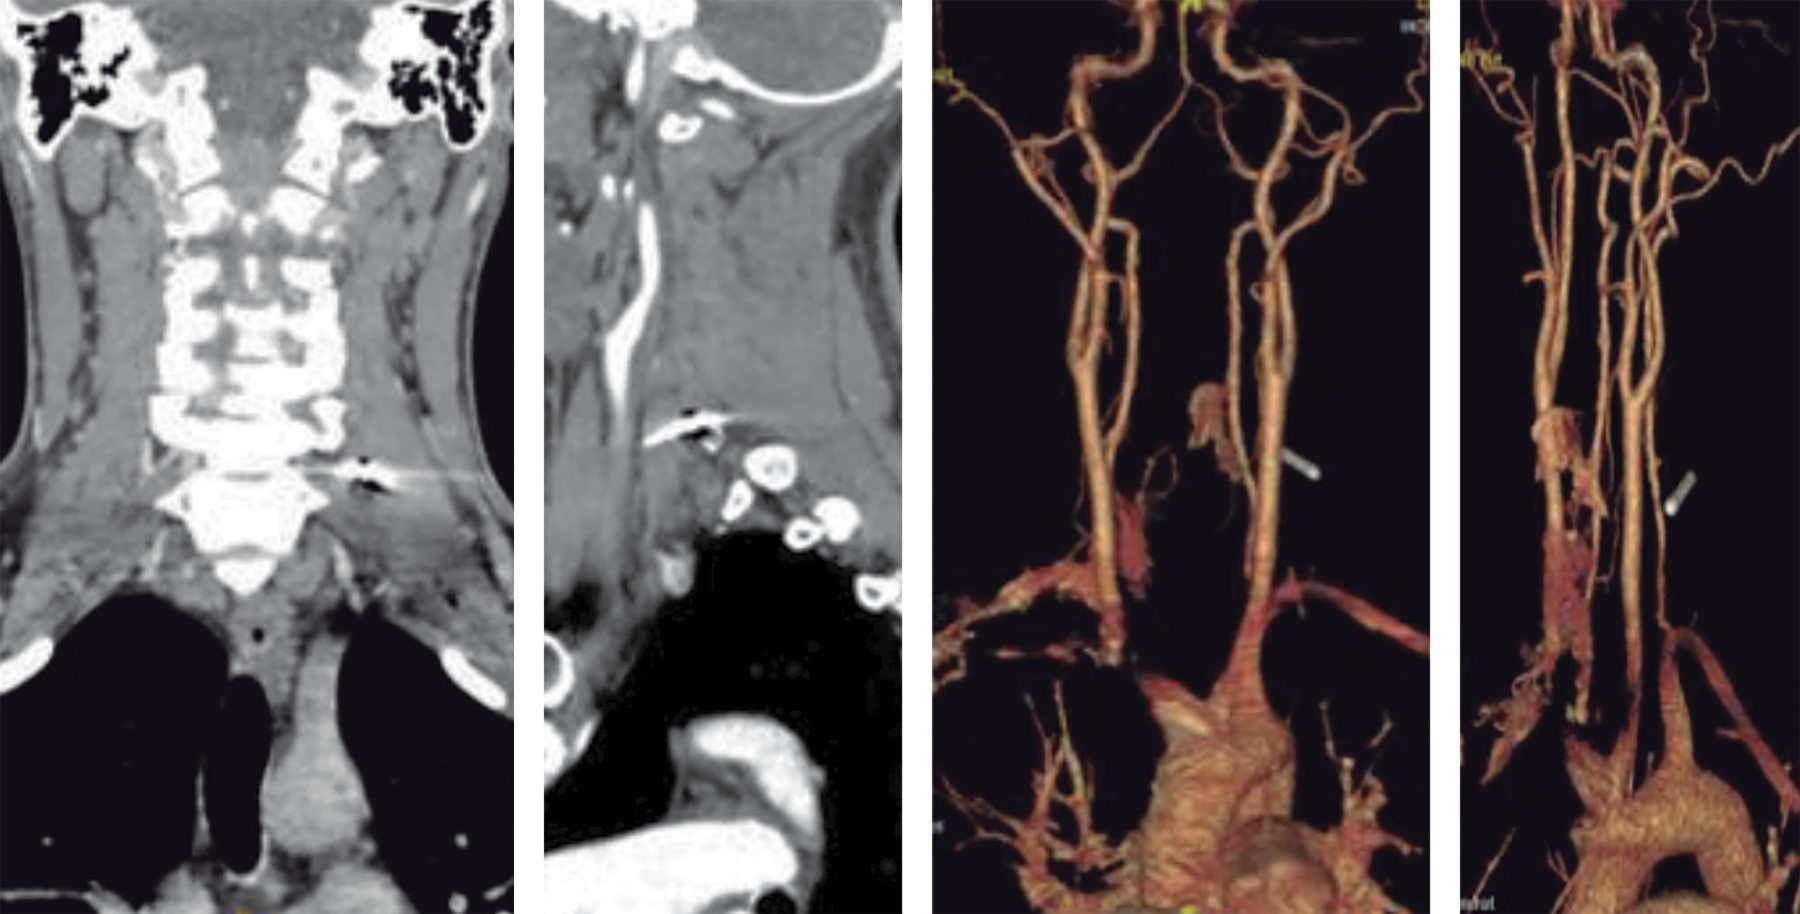

En radiografía anteroposterior cervicotorácica se evidencia cuerpo extraño metálico a nivel C6-C7 izquierdo (Figura 6). En imágenes tomográficas se observa cuerpo extraño metálico a nivel de apófisis transversa izquierda de C7 (Figura 7). Se realiza angiotomografía en la que se evidencia proximidad de cuerpo extraño a grandes vasos, con integridad de los mismos (Figura 8). Se realizó abordaje cervical anterolateral izquierdo a través de plexo cervicobraquial y disección neurovascular; con ayuda de intensificador de imágenes, se localizó el cuerpo extraño en apófisis transversa de C7 izquierda, con posterior extracción sin complicaciones (Figura 9). El paciente evolucionó favorablemente sin déficit neurológico; como protocolo se indicó antibioticoterapia por tratarse de cuerpo extraño.